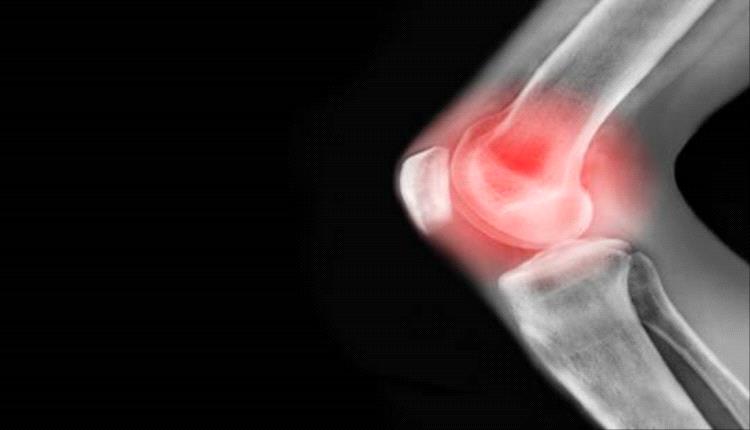

ما أسباب آلام الركبة وكيف يمكن علاجها؟!

يمكن أن يؤثر ألم الركبة المزمن على نشاطك، ويقول الخبراء إن التمارين الأساسية يمكن أن تساعد بشكل كبير في معظم مشاكل الركبة.

وفي معظم الحالات، يتمثل سبب آلام الركبة في الصدمة الناجمة عن إصابة رياضية أو إصابة في العمل.

ويعد تلف الغضروف داخل الركبة وتمزق الأربطة، من الإصابات الشائعة التي تحدث بسبب الصدمة.

وفي حين أن تمزق الغضروف يمكن أن يشفى من تلقاء نفسه، إلا أن الخبراء يحذرون من أن تلف الأربطة قد يتطلب إجراء عملية جراحية.

لكن الخبراء يقولون إن السبب الأكثر شيوعا لألم الركبة يختلف باختلاف العمر.

وغالبا ما يكون الألم ناجما عن إصابة أو حركات مفاجئة تضع ضغطا على الركبة، ما يؤدي إلى التواء أو شد أربطة الركبة، أو تمزق الغضروف أو التهاب الأوتار، وفقا للبروفيسور كارين باركر، خبيرة العلاج الطبيعي في جامعة أكسفورد.